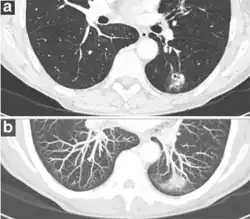

- In case of subsolid nodules, being part solid has a higher risk of cancer than being purely ground glass opacity.

- Part solid nodule.[9]

- Ground glass opacity nodule.[9]